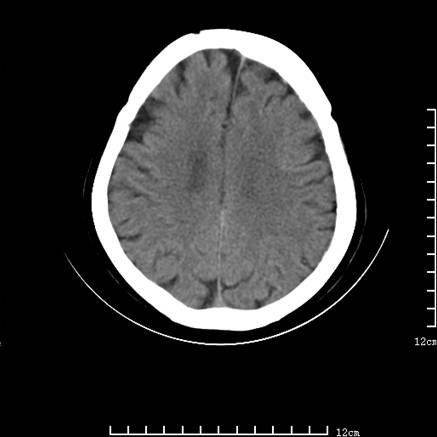

标题: V0514:女,72岁,偶有头晕,自诉记忆力减退,来诊。 [打印本页]

标题: V0514:女,72岁,偶有头晕,自诉记忆力减退,来诊。

2、脑萎缩ct表现。

垂体腺瘤可能性大!另:轻度脑萎缩!

考虑垂体腺瘤可能性大。脑萎缩。

考虑------垂体腺瘤可能性大----脑萎缩

考虑垂体腺瘤可能性大。脑萎缩。  建议mri 检查